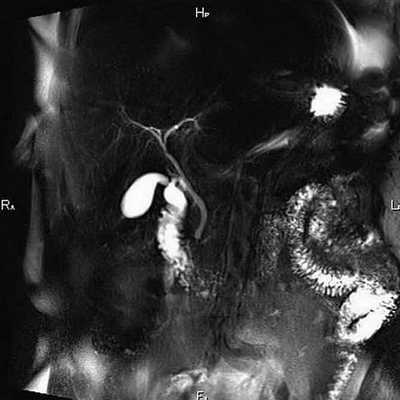

Томограмма желчевыводящих протоков

МРТ холангиография позволяет оценить состояние желчного пузыря и протоков без использования инвазивных мер. Исключением является сканирование с контрастным усилением, когда пациенту внутривенно вводят препарат на основе растворимых солей (хелатов) гадолиния. Вещество отличается низкой токсичностью, гипоаллергенностью и выводится из организма естественным путем.

Опухоль Клацкина на снимках МР-холангиографии